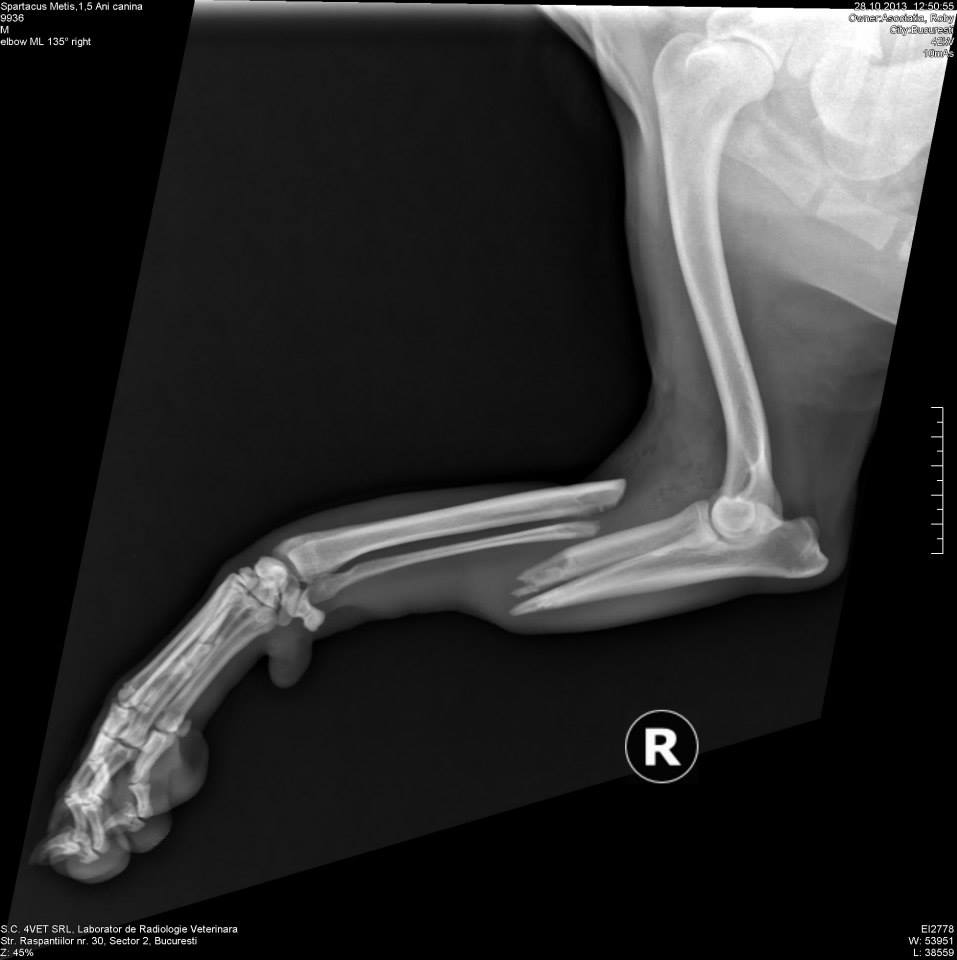

1) fractura cavitatea acetabulara dr.

2) fractura completa oblica diafiza 1/3 mediana radius si ulna deschisa

3) fractura cominutiva diafiza 1/3 proximala tibie si fibula membru posterior dr.